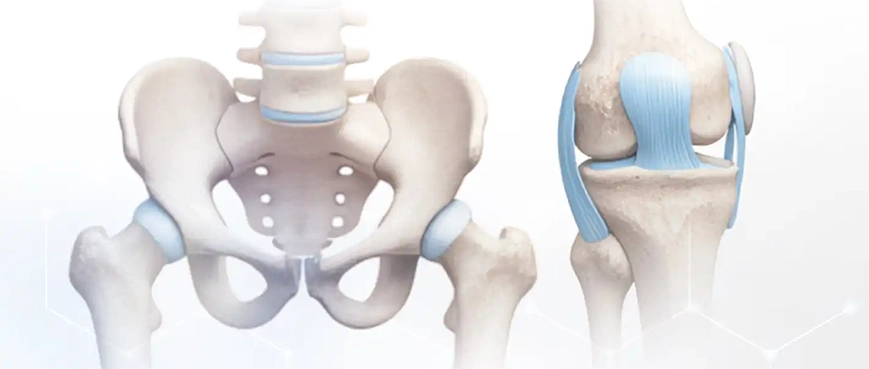

With the development of medicine and high technologies, robotic systems are increasingly entering orthopedics. This innovative method is used for prosthetic operations on the hip and knee joints. Operation planning, analysis of imaging studies, and the actual performance of the procedure are carried out with the help of robotic systems under the supervision and control of the surgeon. This guarantees high precision and safety, even in complex cases.

Placing the prosthesis in an anatomically ideal position slows down the processes of wear and loosening, which extends the implant's life and reduces the risk of discomfort or revision. The entire process is performed by the surgeon, while the robotic system serves for navigation and precise control. Practicing robot-assisted surgery requires special training and certification.

The result is an ideal match between the implant and the anatomy, stability, and natural movement after surgery.